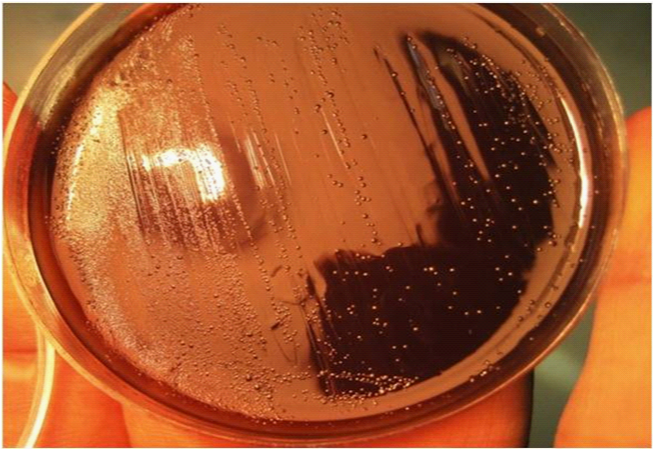

A 45-year-old woman had been admitted to the hospital presented with vomiting and epigastric pain of seven months duration and without specific histories in her family. A gastroduodenoscopy was then performed, and revealed two active duodenal ulcers, both measuring 10mm in size. Furthermore, histopathological examination showed an acute inflammation and H. pylori infection. Subsequent bacterial culture and PCR assay confirmed identity of H. pylori infection.5 Thus, she was treated for fourteen days with H. pylori standard therapy based on proton pump inhibitor (PPI)-amoxicillin-clarithromycin. Because of the likely poor patient adherence of medication, no clear records were available about her first admission. Due to absence of the patient and intense emotional stress, clearance of H. pylori infection after first-line therapy was not confirmed by a negative 13C-urea breath test or even a negative stool antigen test. Strikingly, 10months later, she again referred to the hospital due to the intense epigastric pain. Endoscopic findings confirmed new 11mm duodenal ulcer. Because of positive rapid urease test (RUT) at endoscopic room, further microbiological analysis prescribed.6 Since possible risk of mix infection, bacterial culture was performed to investigate H. pylori mix infections. In brief, from original plate (Figure 1), five different colonies were picked and restreaked in new plates according to the standard protocols.7,6 PCR of virulence genes, (e.g. cagA, iceA1, homB, babA2 and cagE) were carried out to detect and draw genetic variability panel of those H. pylori strains.8–10 Primer sequences, sizes, and conditions of PCR amplifications of the glmM gene for detection and confirmation of H. pylori and the other genes (i.e., homB, cagA, cagE, iceA1 and babA2), were carried out using the conditions described previously (Table 1).6,9,8 This time, after starting second-line therapy (levofloxacin-based therapy), within 4weeks, positive 13C-urea breath test became negative and her duodenal ulcer was also completely cured.11 The presence of H. pylori virulence genes was directly determined by specific sensitive PCR method, then results were compared per single strain (Table 2). The distribution of various H. pylori genotypes as shown in Table 2 indicates presence of mix infections. In a follow up system for this interesting case of up to 12months, no new abdominal pain, vomiting or any evidence to H. pylori infection were observed.

Figure 1 Original plate harboring at least 5 different H. pylori strains isolated from 45-years-old women.